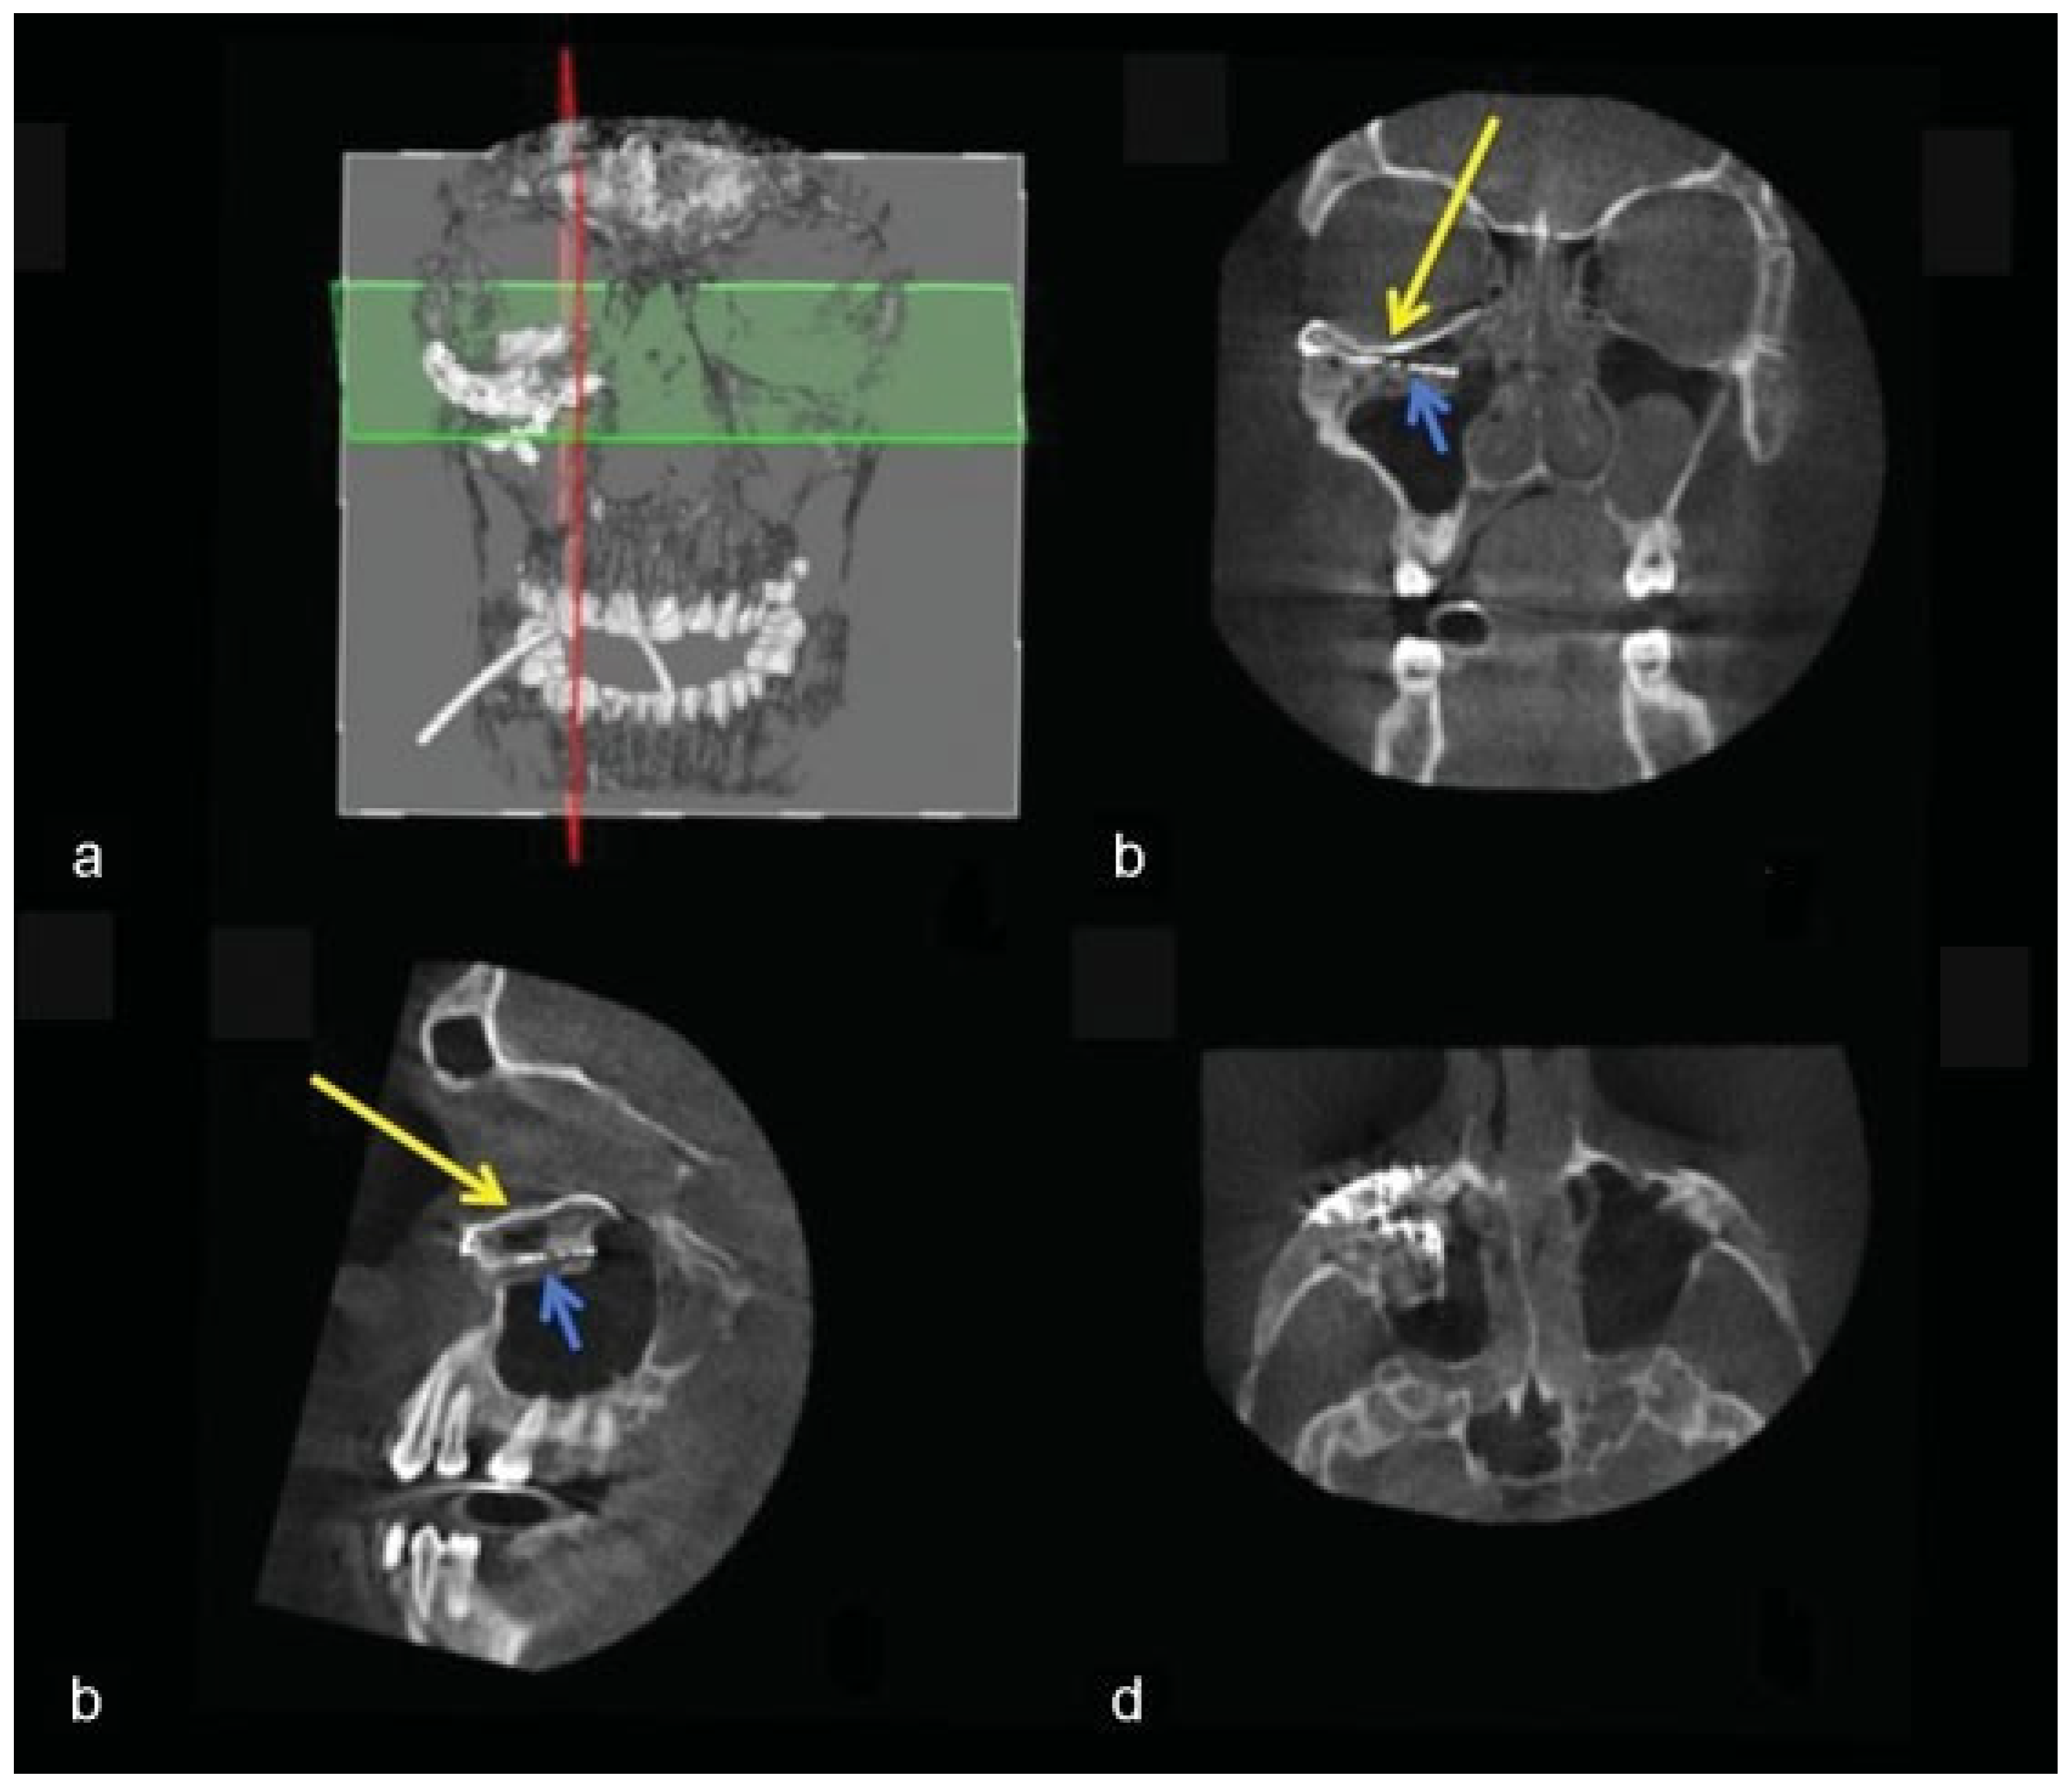

Figure 1. Case 3: The two-piece puzzle design with overlap at the rim. Positions of implant screw holes took into account the underlying structures (orbital mesh, infraorbital nerve, lacrimal system). Information regarding the ideal screw length was provided.

A 28-year-old man was referred with disabling diplopia and severe globe malposition after two repairs of an impure orbital floor fracture using a stock titanium orbital mesh plate (►Figure 9). He had been hit by a pulley in a work accident. The presence of the previously inserted titanium mesh slightly hindered implant design because of the scatter effect on CT scan. Mirroring revealed a height difference of 7 mm between the unaffected side and the mesh on the affected side (►Figure 10, Figure 11 and Figure 12). The 3D model had to take into account the lower position of the orbital rim, and the screw position was based on the amount of remaining bone and positions of the mesh, infraorbital canal, and lacrimal system. The porous implants were printed with a double tongue-in-groove design (►Figure 1 and Figure 10). The puzzle-piece design allowed precise fit between the first and second implants (►Figure 12). Anterior flanges were not necessary as the shape of the reconstructed infraorbital rim provided anteroposterior guidance. Slight diplopia in extreme upward gaze and lagophthalmos remained because of previous fibrosis (►Figure 9).